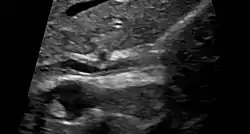

Die eindeutigste Methode ist die Darstellung der Gallenwege mittels ERC (endoskopisch retrograde Cholangiographie). Wegen der relativ hohen Komplikationsrate ist aber heute die bildgebende Methode der Wahl die MRCP (Magnetresonanz-Cholangiopankreatikographie). Auch Autoantikörper, die sogenannten pANCA (perinukleäre antineutrophile zytoplasmatische Antikörper) können typischerweise nachgewiesen werden, sie treten aber nur bei 70 % der Patienten auf.